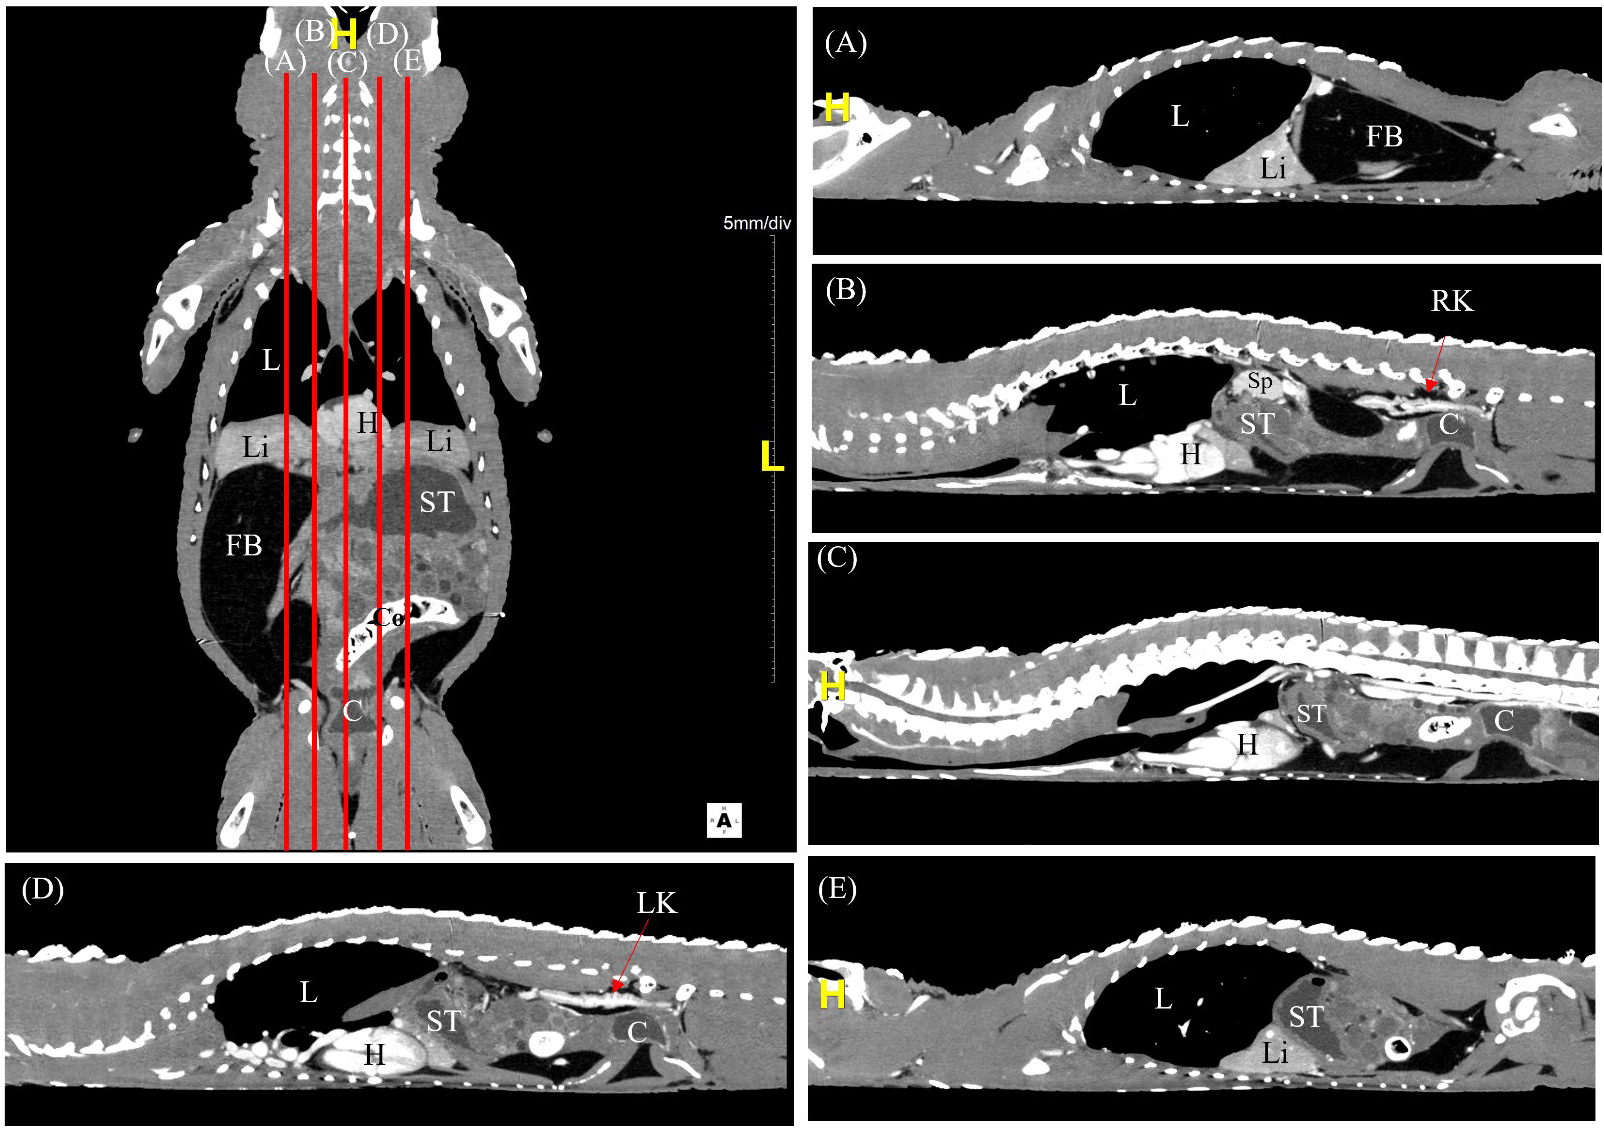

The CT scans were carried out smoothly with no side effects from mechanical restraint and CT contrast injection via the occipital venous sinus. The post-contrast time, determined by the washout of contrast medium from kidneys, ranged between 8 to 10 minutes to obtain images of the coelomic organs with adequate contrast perfusion (Figure 2). The quality of the reconstructed CT images was consistent between different species.

Figure 2

A labelled coronal contrast-enhanced CT image of an Alligator sinensis with corresponding parasagittal (A, B, D, E) and mid-sagittal (C) views in soft tissue window. [Highlighted in yellow, H, head/cranial; L, left; C, cloaca; Co, colon; FB, fat body; H, heart; L, lung; Li, liver; LK, left kidney; RK, right kidney; ST, stomach; Sp, spleen].